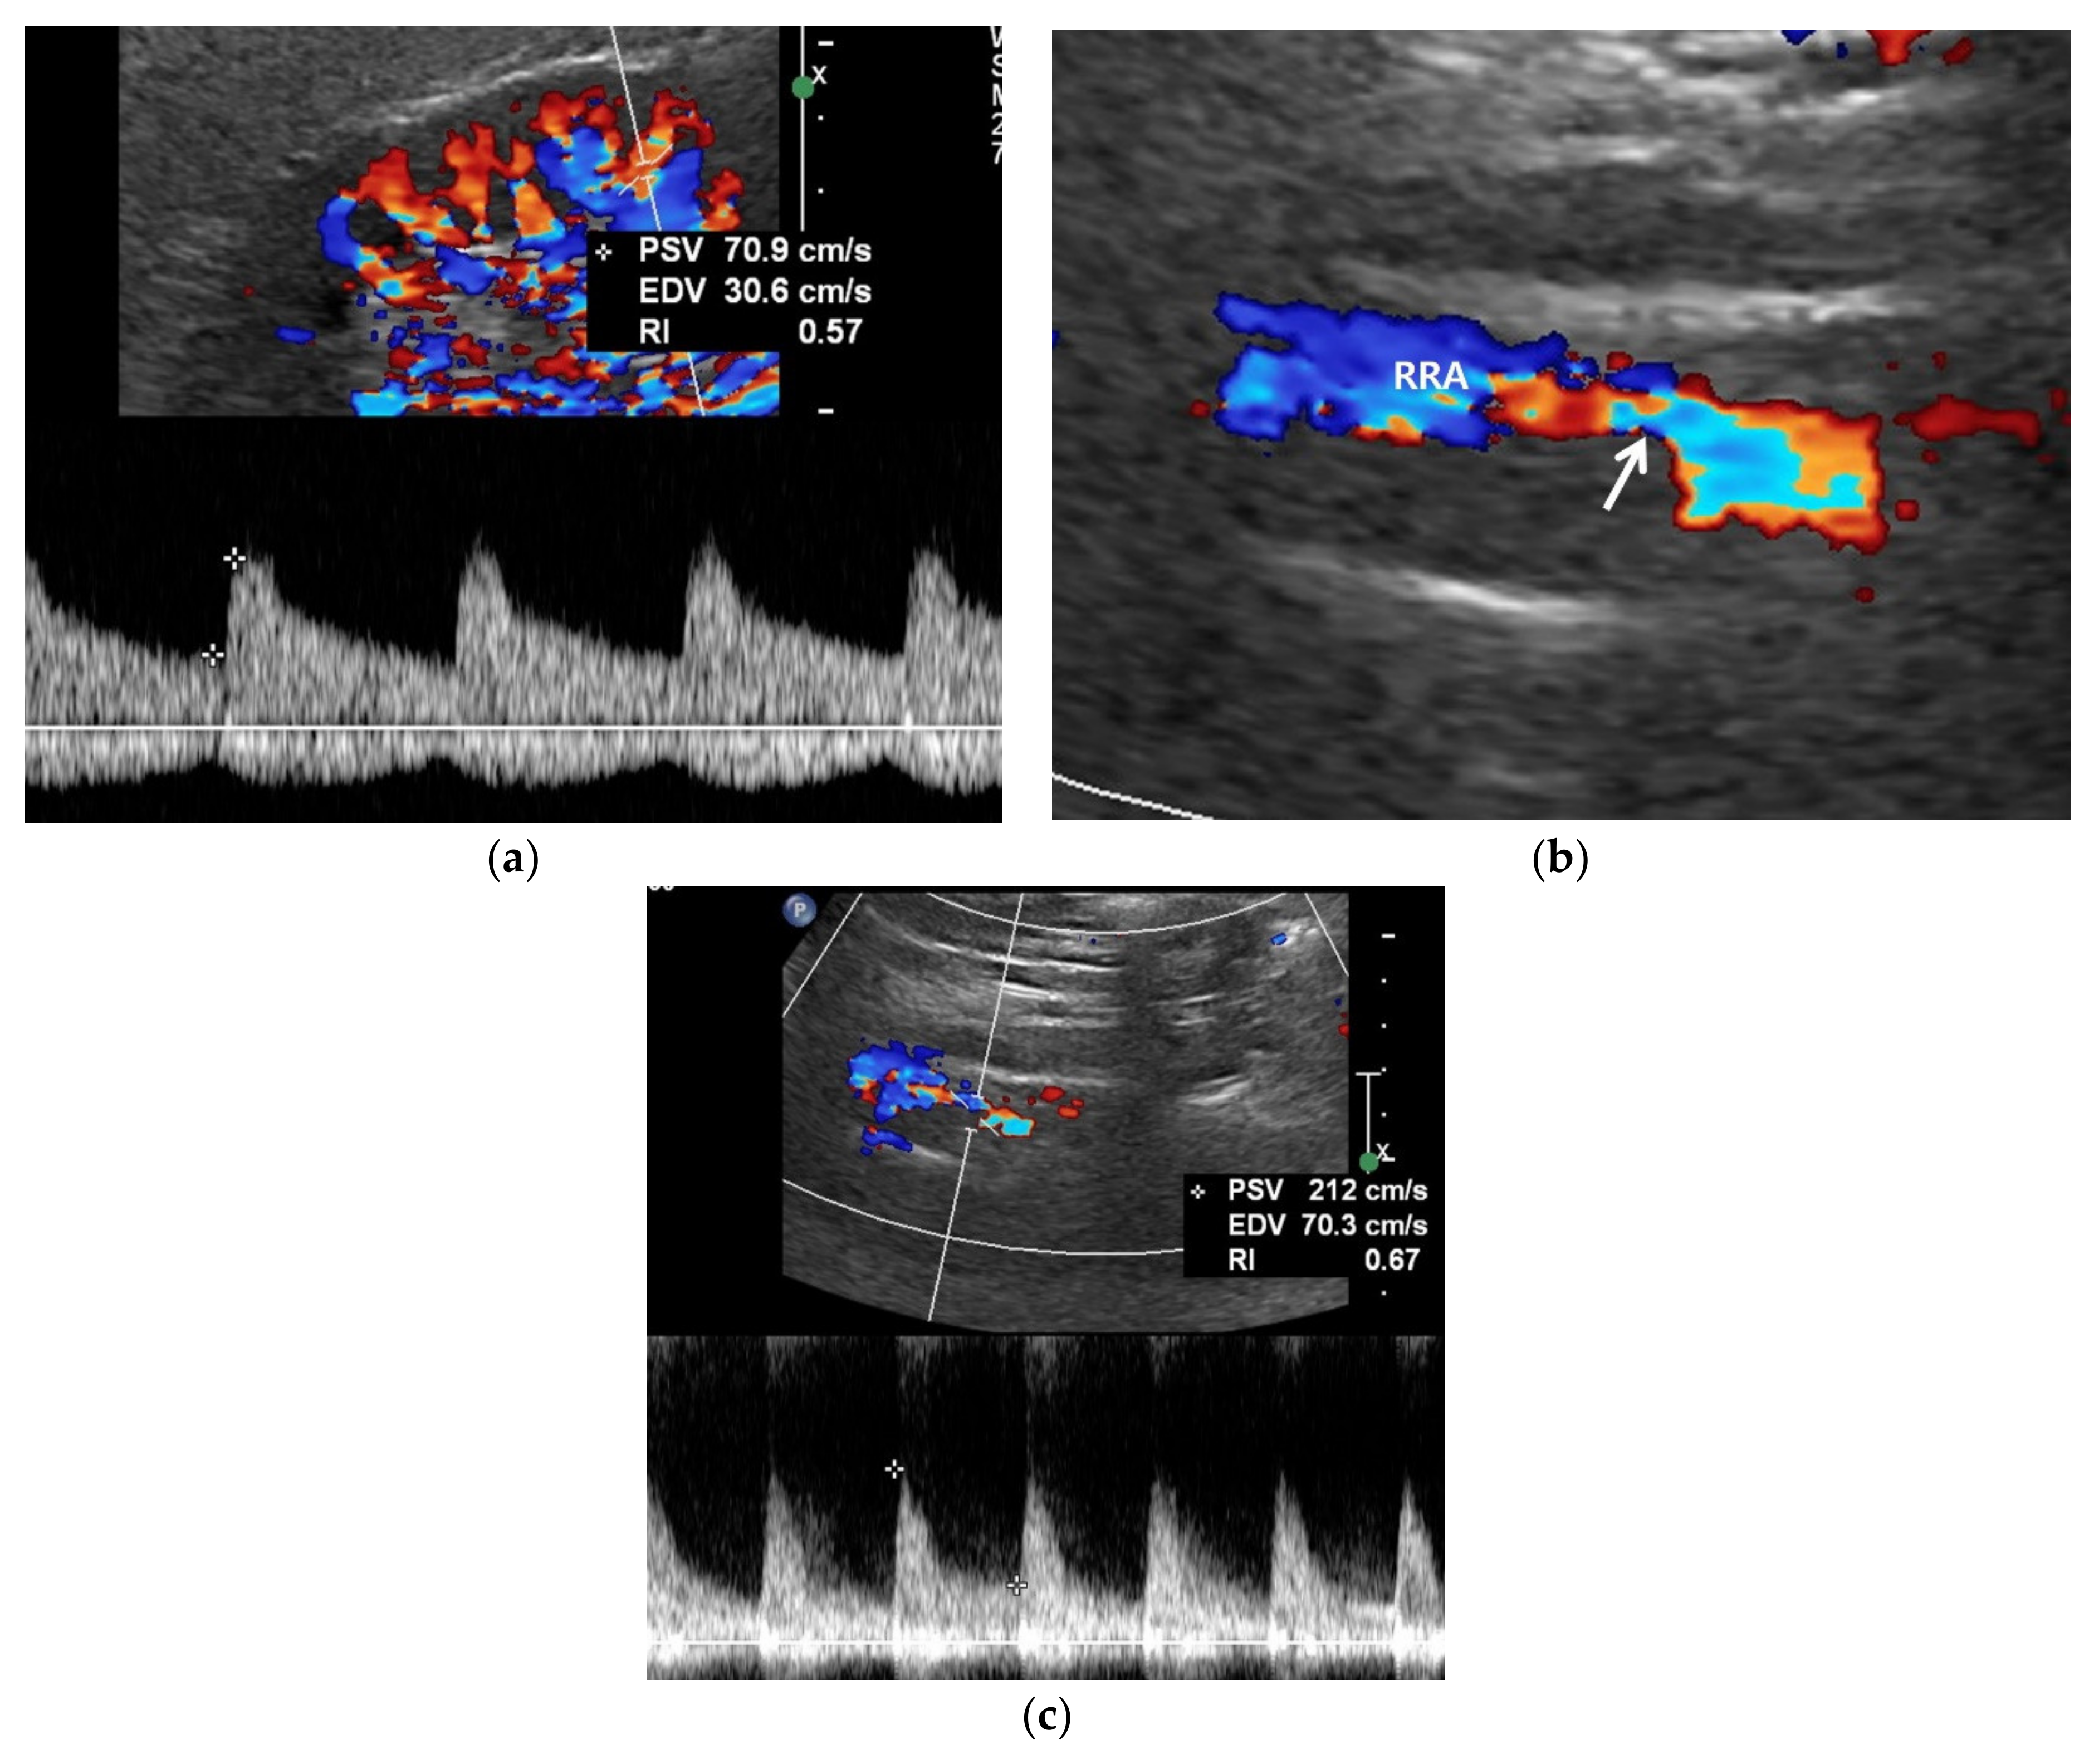

Figure 3.

RAS-positive renal artery US in a 20-year-old man with negative renal US. (a) Spectral Doppler US does not show pulsus tardus and parvus pattern in the right kidney even though the size (11 cm) and echogenicity appear normal. (b) Color Doppler US shows a focal stenosis (arrow) in the proximal right renal artery (RRA), suggesting RAS. (c) Spectral Doppler US shows a high peak systolic velocity (PSV) (212 cm/s) in the stenotic right renal artery.

Color Doppler US of the kidneys is not an ideal approach for detecting RAS. Renal perfusion can be normal in early stage RAS (Figure 4) and decreases in intermediate or late-stage RAS. Renal perfusion is an indirect finding suggesting RAS. Accordingly, it is not adequately sensitive for detecting early stage RAS.

Figure 4.

A high reno-aortic PSV ratio in a 78-year-old man. (a) Spectral Doppler US shows that a PSV is measured 83 cm/s 1–2 cm below the origin of superior mesenteric artery. (b) Spectral Doppler US shows that a PSV is measured 318 cm/s in the poststenotic area, showing turbulence flow. The frequency shift in the proximal left renal artery (arrow) is not sufficient to precisely quantify. The high-PSV RAR is more than 3.8 (318/83) because the PSV in the RAS should be higher than that in the poststenotic area.

5.3. Spectral Doppler US

Spectral Doppler US quantitatively measures the velocity of blood flow in the stenotic renal artery (Table 4). The peak systolic velocity (PSV) within the stenotic renal artery is frequently more than 180–200 cm/s [4,22,23,24,25,48] (Figure 2 and Figure 3). If PSV is more than 180 cm/s, the sensitivity and specificity for RAS range from 85–97% and 72–98%, respectively [24,25,28,31]. In case of unilateral RAS, PSV is significantly different between the two renal arteries. At this point, two simple concepts should be kept in mind: first, the normal PSV values in normal renal arteries without stenosis (about 70–100 cm/s), and, second, angle correction is essential to obtain reproducible and accurate measurements of PSVs. If the PSV of the renal artery is ≥3.5-fold that of the aorta (renal-to-aorta ratio (RAR)), it can suggest RAS [26,27,29,49] (Figure 4). The PSV RAR is another good indicator for identifying RAS. If RAR is 3.5 or greater, the sensitivity and specificity ranges are 91–92% and 71–95%, respectively [26,27,29]. It is important to determine where PSV is measured within the aorta because it differs by region-of-interest location. First, radiologists or sonographers should find the origin of the superior mesenteric artery (SMA) during the sagittal US scan; then, the PSV region of interest should be 1–2 cm below the SMA because the renal arteries are located below the origin of the SMA.

The frequency shift from the stenotic artery is not easy to detect with spectral Doppler US as it tends to be small (Figure 2 and Figure 3). There are some technical tips in assessing RAS: First, the critical angle between the renal artery flow and US from transducer should be observed when a good spectrum of arterial flow is not obtained. The optimal critical angle should be kept at 30–60° for detecting a good frequency shift [48]. Second, the sample volume size should be higher than that of the RAS to oversample frequency shifts. The renal artery spectrum can be identified by means of evaluating the flow direction and spectral pattern from among the various spectra given by arteries and veins. Third, the PSV of the renal artery should be measured in the poststenotic dilatation when a good spectrum cannot be obtained in the stenosis (Figure 2 and Figure 3). If the PSV is more than 180–200 cm/s, it will be higher in the stenotic artery. If RAS is severe, the frequency shifts are too weak to directly detect from the stenotic artery [23,49].